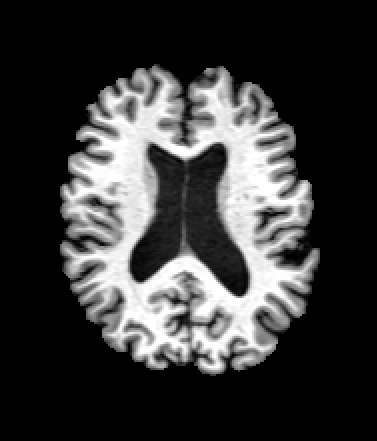

A trained MetaVoxel model can be unconditionally sampled by drawing Gaussian or categorical noise for each variable at timestep , and iteratively apply the denoising network until reaching . Unlike conventional diffusion models that focus solely on image generation, MetaVoxel can generate coherent synthetic patient profiles from the joint distribution , as shown in Figure 2.

| Age: 64.0 | Age: 53.8 | Age: 70.9 | Age: 76.9 |

| Sex: Male | Sex: Female | Sex: Female | Sex: Male |

![]() |

| Age: 80.9 | Age: 77.7 | Age: 73.2 | Age: 84.6 |

| Sex: Male | Sex: Female | Sex: Female | Sex: Female |